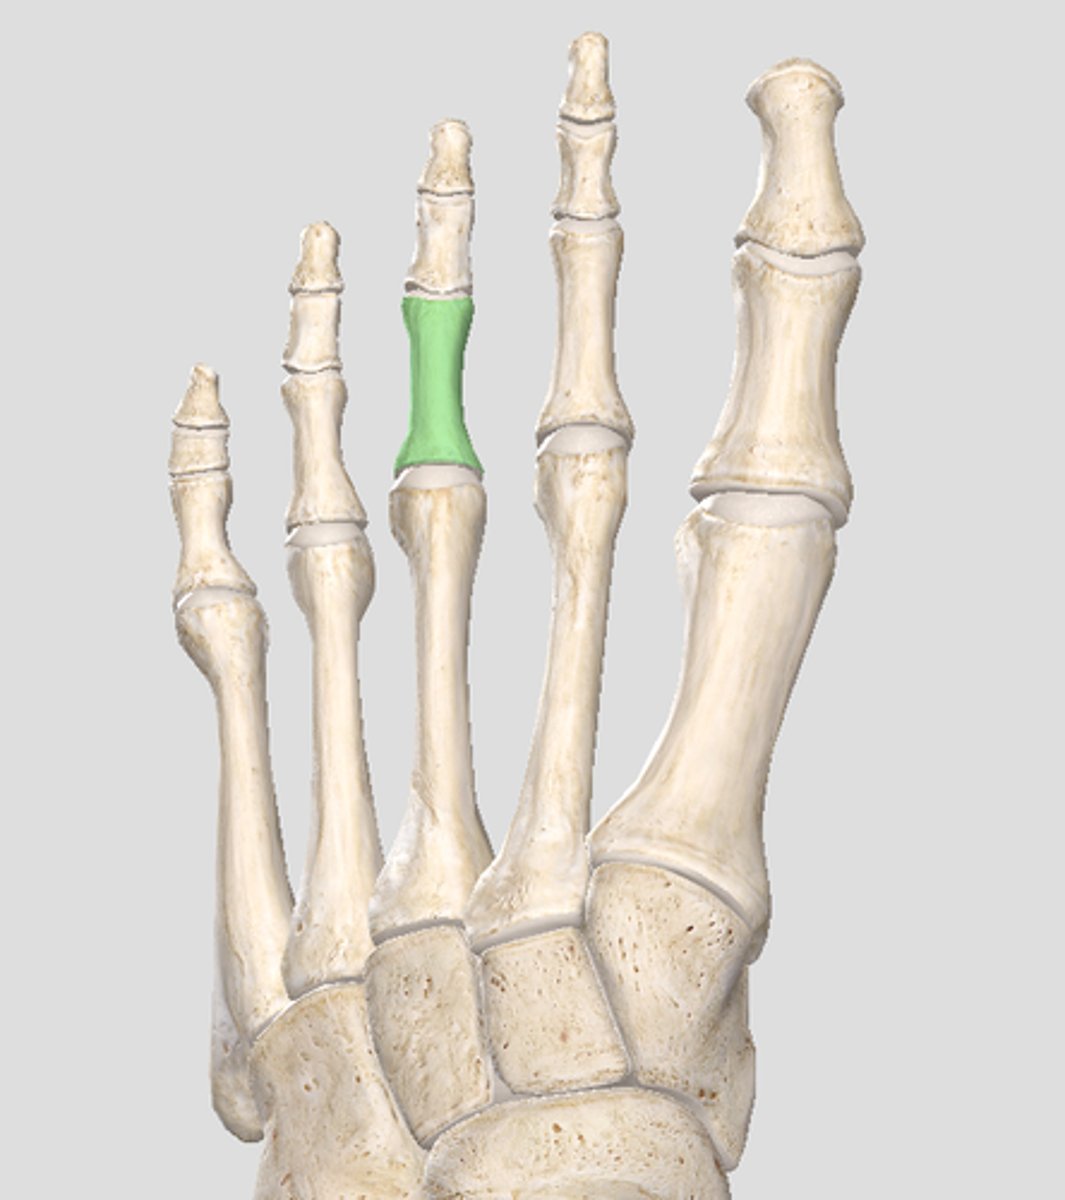

Middle phalanx of digit 3

Distal phalanx of digit 3